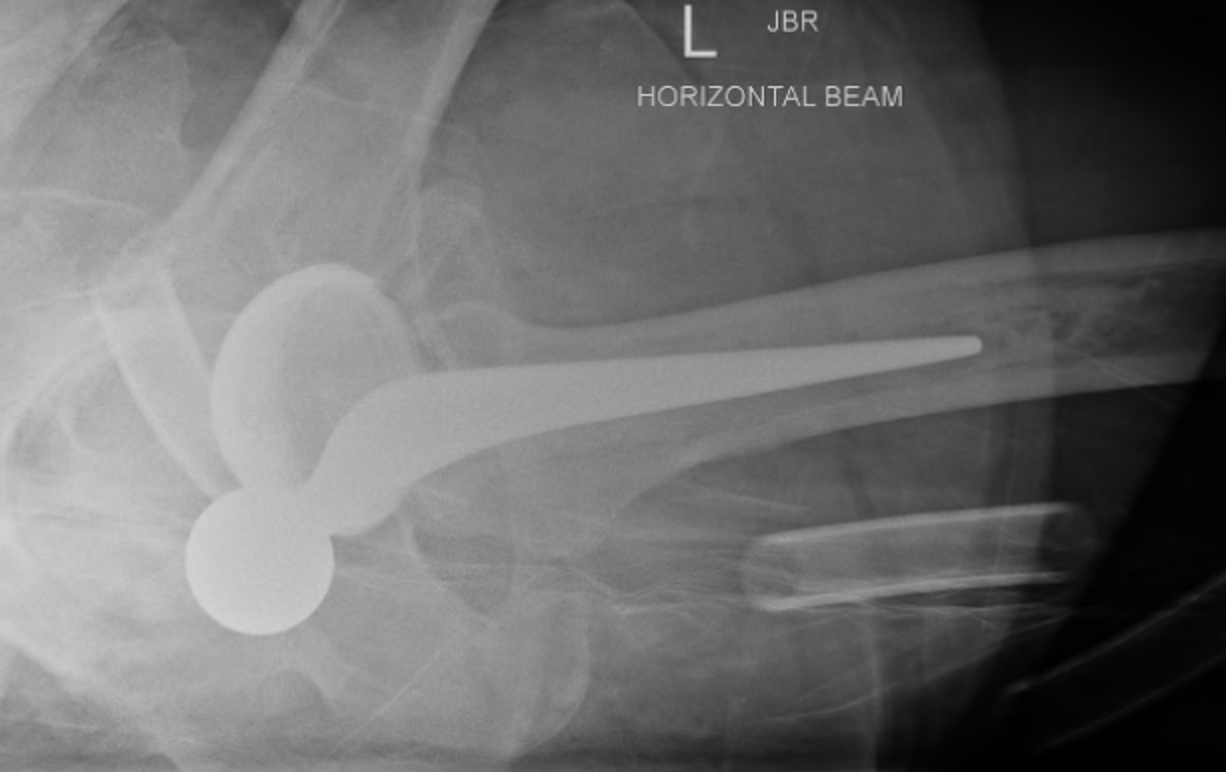

Posterior dislocation

- hip flexed, adducted, internally rotated